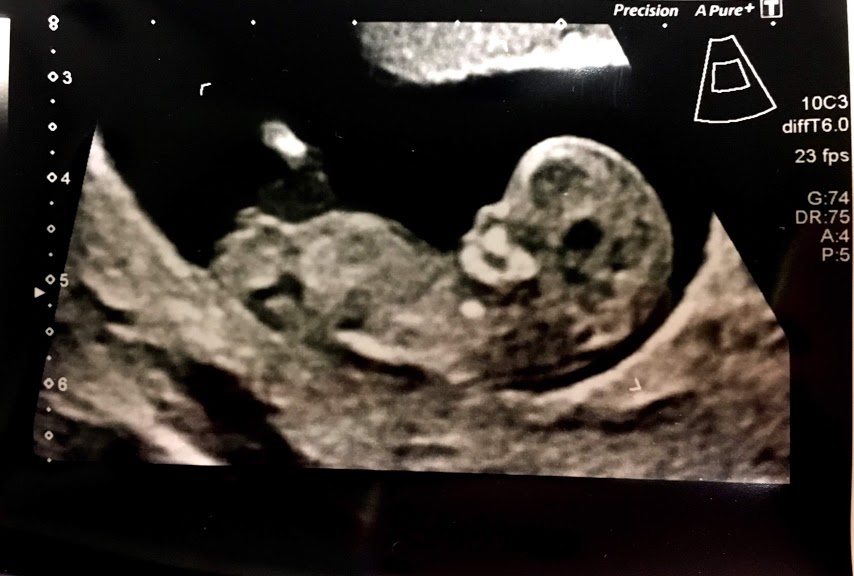

We maken standaard bij elke zwangere een echo rond de 10-13 weken, de termijnecho Onze resultaten van de 13 weken echo's hebben we maanden lang vergeleken met dezelfde kindjes bij 16 weken

.. 13 weken echo jongen of meisje volgens nub theorie? Babybytes. De hoek is alleen bij jongens iets groter dan bij meisjes Zoals de naam al zegt, vindt deze controle plaats rond 13 weken zwangerschap